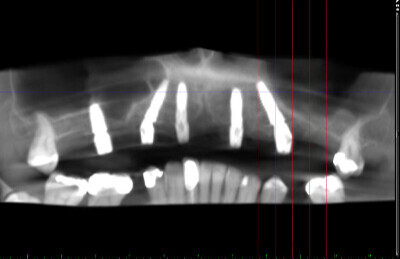

Navigovaná chirurgia, 5 implantátov

Autor práce Dr. Michal Repaši

Zubný technik Vasil Csopej